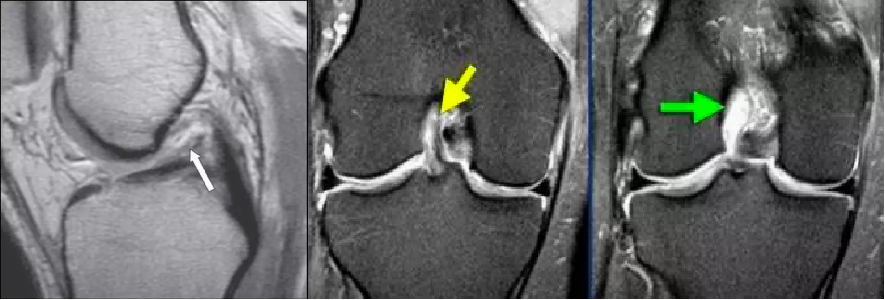

美国医学会,交交叉韧带损伤的分级标准,在 MR 上前交叉韧带损伤可分为 3 级损伤:

1 级:前交叉韧带纤维束拉伤或隐匿损伤

仅有韧带内结构改变。在 T1 和 T2 加权序列上,韧带信号增高,但韧带的纤维束完整,韧带形状、厚度、长度无改变。

2 级:前交叉韧带部分损伤

在 T1 和 T2 加权序列上都有高信号改变,且有韧带增厚(肿胀或出血所致),韧带外形和纤维不规则或部分不连续。